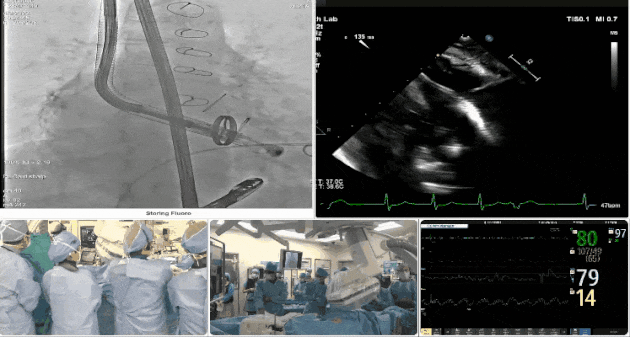

術后DSA、超聲顯示人工瓣膜穩定性良好,瓣葉啟閉正常,無瓣周漏

術中TEE觀察夾持件的位置

術后DSA

術后超聲評估瓣膜穩定性良好,無瓣周漏

手術過程

術者采用經右側頸靜脈入路的方式將輸送器送入患者心臟內,在TEE及DSA引導下調整輸送器頭端角度,使得輸送器與三尖瓣瓣環平面垂直。在輸送器進入右心室后釋放室間隔錨定裝置,而后釋放瓣葉夾持件(2個耳片結構)成垂直狀態。在TEE及DSA確定夾持件固定至三尖瓣葉根部且位于右室側后釋放人工瓣心房側盤片。隨后調整瓣膜同軸性以及室間隔錨定件位置(貼合室間隔),前推藏針管并固定,進而釋放室間隔錨定裝置,并再次確認瓣膜位置、穩定性及同軸性,合攏輸送鞘后撤出輸送器,最終順利完成LuX-Valve Plus人工三尖瓣瓣膜的植入。